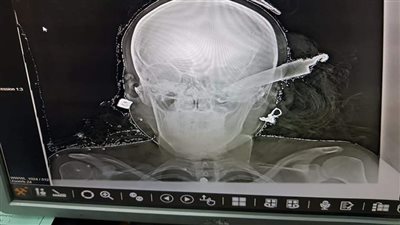

بالانتقال والفحص تبين قيام "جورج. س. ي"، 27 عامًا، عامل، قام بقتل كل من: والده المدعو "س. ي" 70 عامًا، ووالدته المدعوة "امال. ن"، 65 عامًا، ونجلي شقيقته الطفلة "إنجي"، 5 سنوات، والطفل "مينا"، 6 شهور، كما أصاب شقيقته المدعوة "مارينا"، 25 عامًا، تم نقلها لمستشفى سوهاج الجامعي.